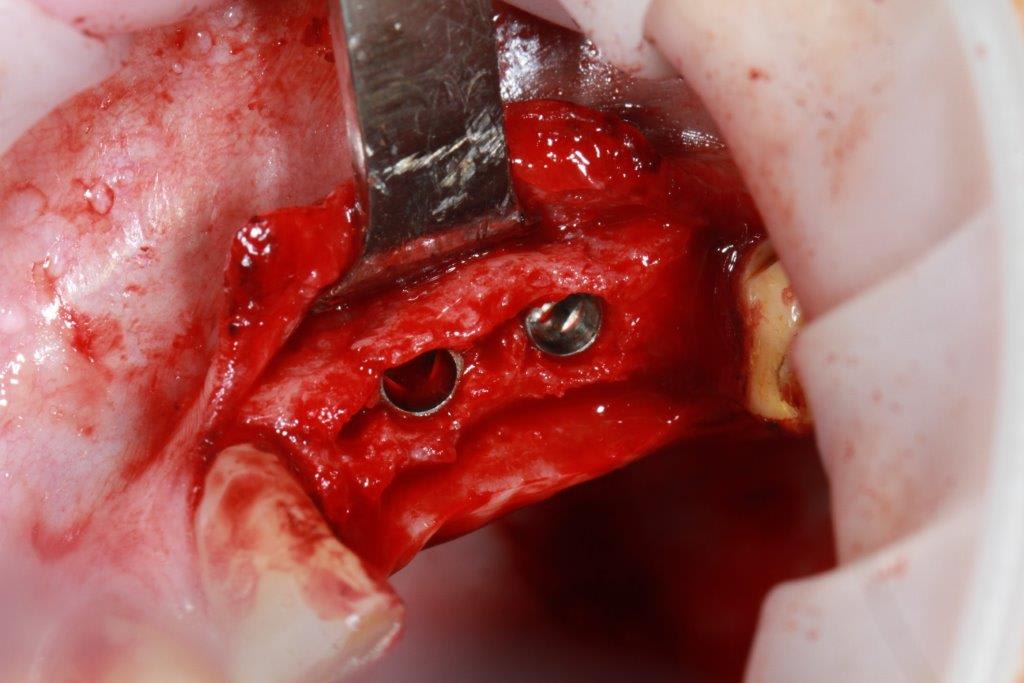

petit cas sympa ancien bridge très mobile....plutôt que d'extraire 25, j'ai déposé la couronne, retraité la dent stabilisation pendant deux mois puis séance d'ostéotension et ce jour pose de deux axioms PX 34120 après expansion...

Pxav, je vois des zones concaves entre les implants et en mesiale, tu laisses les expanseurs pour visser les implants, tu réalises 4 points d'impacte avec les demi-lunes ?

comme je n'ai pas fait de décharges osseuse en vestibulaire, j'ai effectivement travaillé toute la longueur de la crête, mais, là j'ai ôtè les expanseurs avant de visser les implants car ce sont des PX qui ont un apex assez fin, pour des regular j'aurais pratiqué différemment.

en général (99,9% des cas) je ne constate aucune lyse osseusecrestale, ce type de chir. est très douce pour l'os, lame 15, et ostéotomes, pas de forage, pas de consommation d'os, pas d'agression ni de lavage (piezzo), et je fais toujours attention à laisser du sang (sauf pour les photos) ce qui est le meilleur pansement pour l'os.

par contre les axioms doivent être posé en sous crestal, ce qui est fait ici, avec sans doute comme souvent une nécessitè d’ostéotomie, lors de la mise en charge, car il est fréquent que le col implantaire soit recouvert.